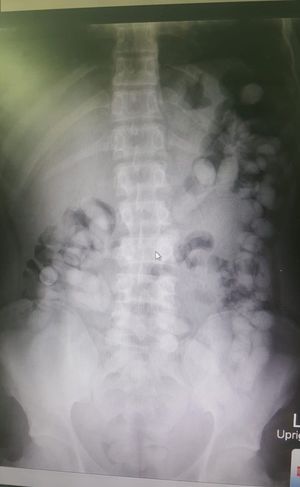

Body packer: This an Individual who ingests wrapped packets of illicit drugs such as cocaine, heroin, amphetamines, ecstasy, marijuana, or hashish to transport them. A person who transports illicit drugs by internal concealment. DDX: Intestinal Obstruction.